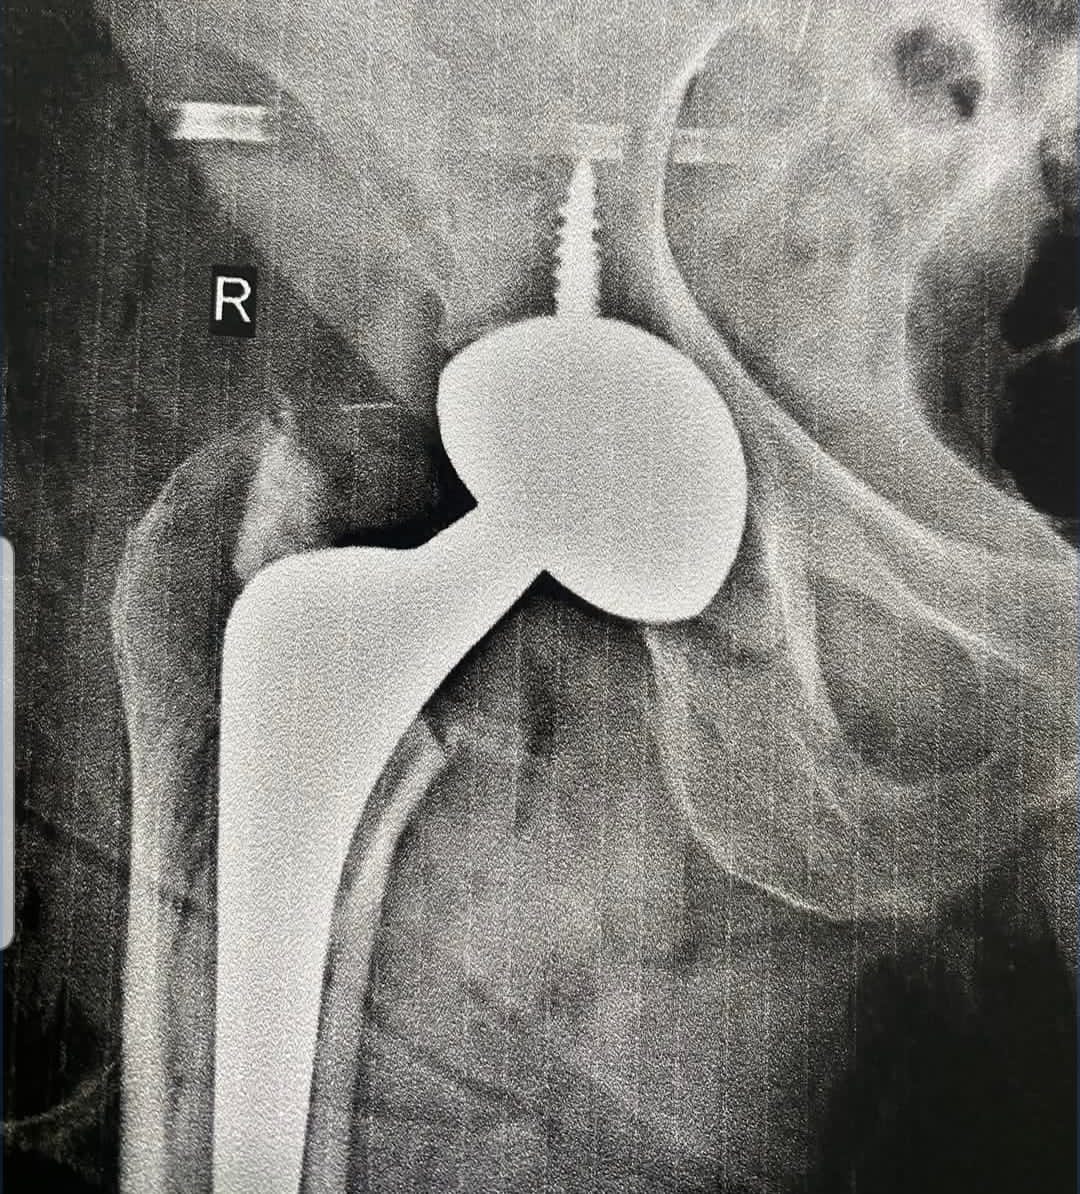

इन सभी चुनौतियों को ध्यान में रखते हुए सर्जरी में विशेष प्रकार के आधुनिक हाइब्रिड, डुअल मोबिलिटी इंप्लांट का उपयोग किया गया। यह तकनीक जोड़ के स्थायित्व को बढ़ाती है और डिसलोकेशन के खतरे को कम करती है। सावधानीपूर्वक योजना और बहु-विषयक समन्वय के साथ की गई इस सर्जरी के सकारात्मक परिणाम सामने आए।

सफल ऑपरेशन के दूसरे ही दिन महिला आत्मनिर्भरता के साथ चलने लगीं और शीघ्र ही उन्हें अस्पताल से छुट्टी दे दी गई। इस सर्जरी में डॉ. विजय शर्मा के साथ डॉ. मनीष गुप्ता और एनेस्थीसिया टीम का महत्वपूर्ण सहयोग रहा।